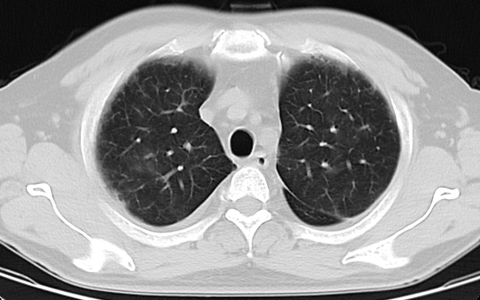

反复发热半月,突出的表现:血小板迅速下降至个位数,肝肾功能不全进展迅速,胆红素增高直胆为主,咯血,呼吸衰竭。患者职业养鱼,近半月来使用菌毒净清洁鱼塘。

血NGS结果:钩端螺旋体感染。